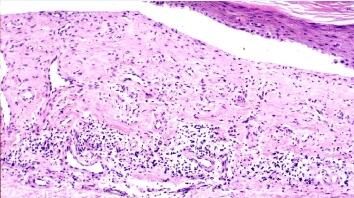

北京京城皮肤医院指出:中毒性表皮坏死松解型药疹为重型药疹,常由磺胺类、解热镇痛类、巴比妥类和抗生素引起。

中毒性表皮坏死松解型药疹特点:

1、急性起病,开始为非特异性表现,常见发热、咽痛和全身不适,病情进展迅速,l-3天后出现皮肤粘膜损害。

2、多系统受累可危及生命,败血症、消化道出血及水电解质紊乱是主要的死亡原因。中性粒*降低常与不良预后相关。

3、人群年发生率约为0.44一1.2/百万,死亡率为30 左右。